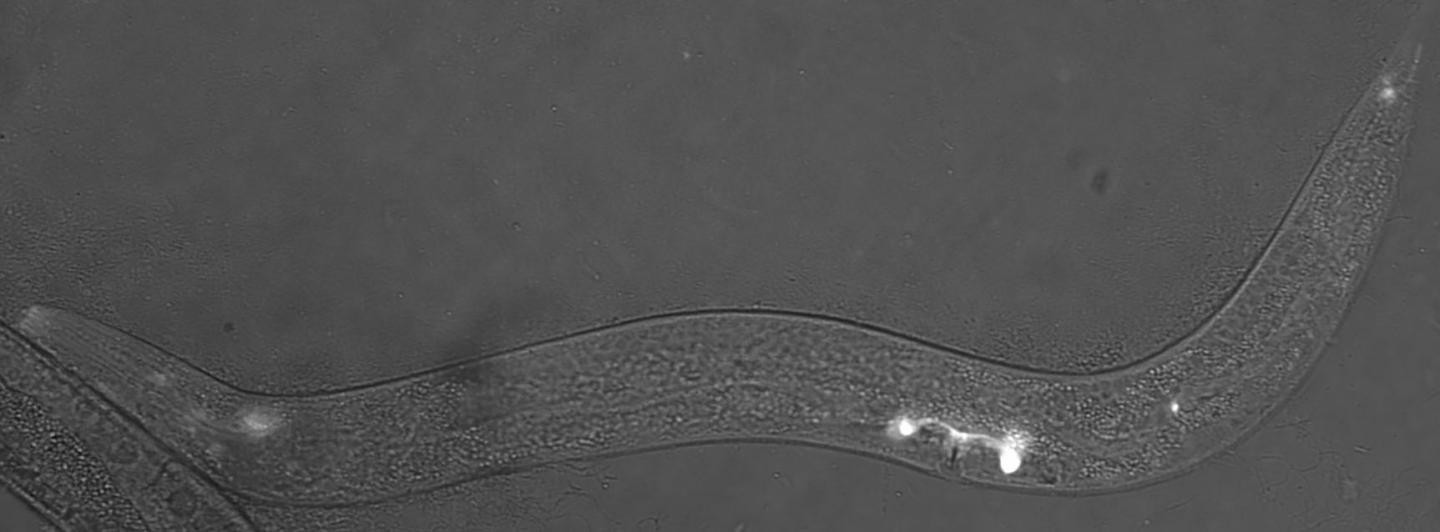

image: Glowing sensory cells in the worm C. elegans that make complement factor H protein.

Dr. Vogel's team found a worm version of complement factor H protein located in the sensory neurons that help the worms detect chemicals, food, touch, and temperature. The protein appeared specifically in the middle region of the sensory neuron's little antennas, known as cilia (that do the work of sensing the environment), just next to another known important antenna protein called inversin. However, in worms bred to lack complement factor H, they found the inversin spread throughout the antennas rather than remaining in the middle of the antennas.